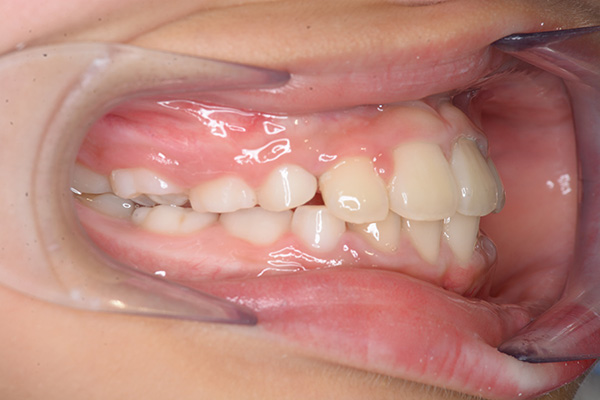

動的治療開始前(9歳7ヵ月)

動的治療開始前

(9歳7ヵ月)

IOP

口腔内所見 over jet -2.5mm、over bite 2.0mm、大臼歯関係はⅠ級 。Hellmanのdental ageはⅡCであり前歯部は反対咬合を呈していた。